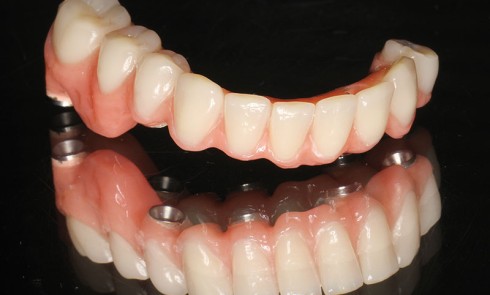

Article réservé à nos abonnés Gestion pragmatique de l’échec implantaire sans déroger à la solution implanto-portée

La pénétration de l’implantologie dentaire dans le tissu professionnel a atteint une phase de maturation. Nombreuses sont les formations offertes...